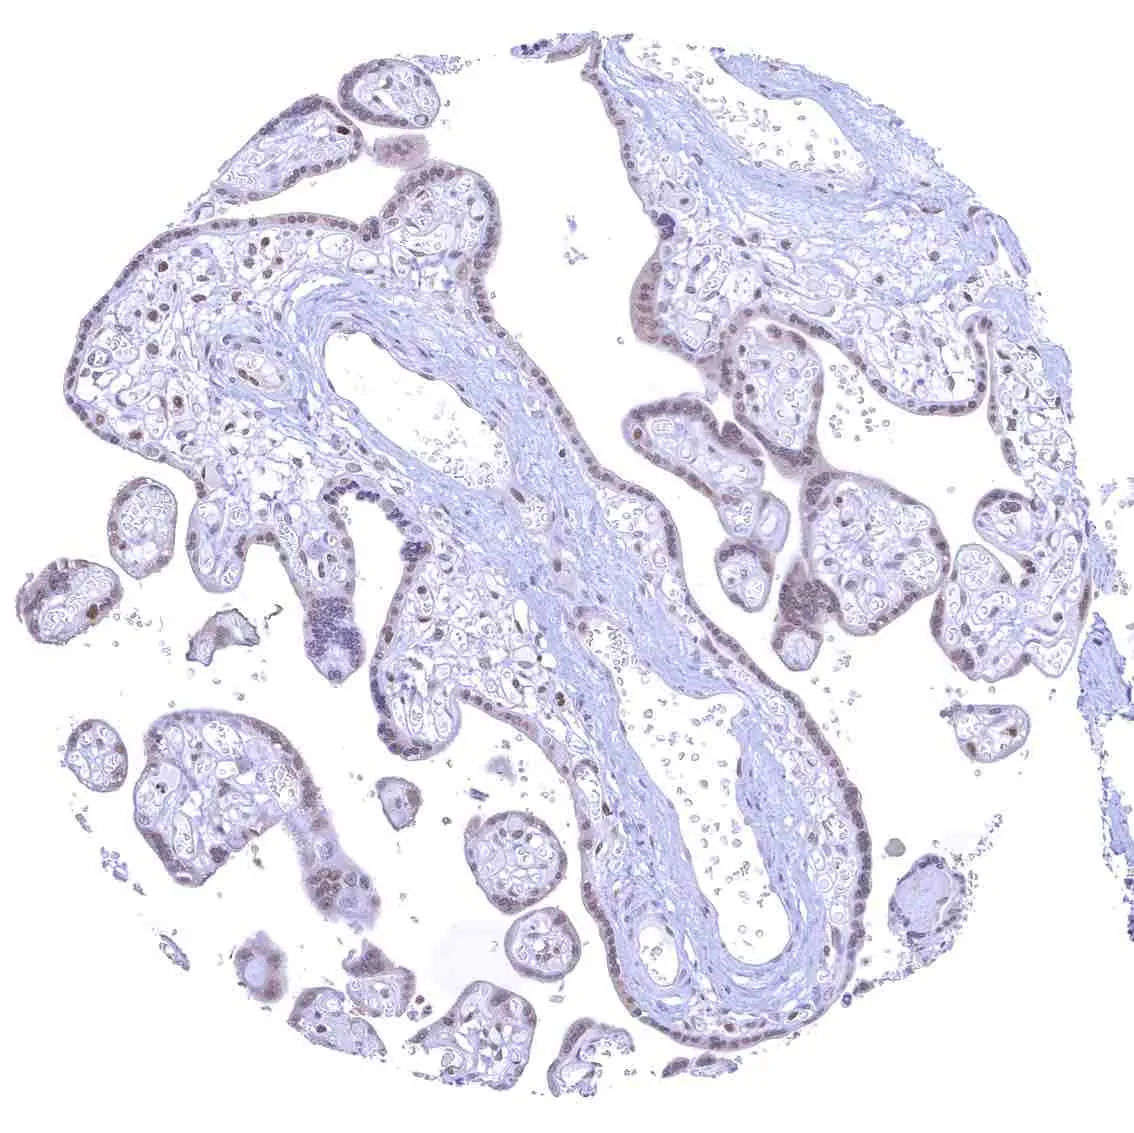

Placenta, early – Strong p27 staining of all nuclei of the syncytiotrophoblast.